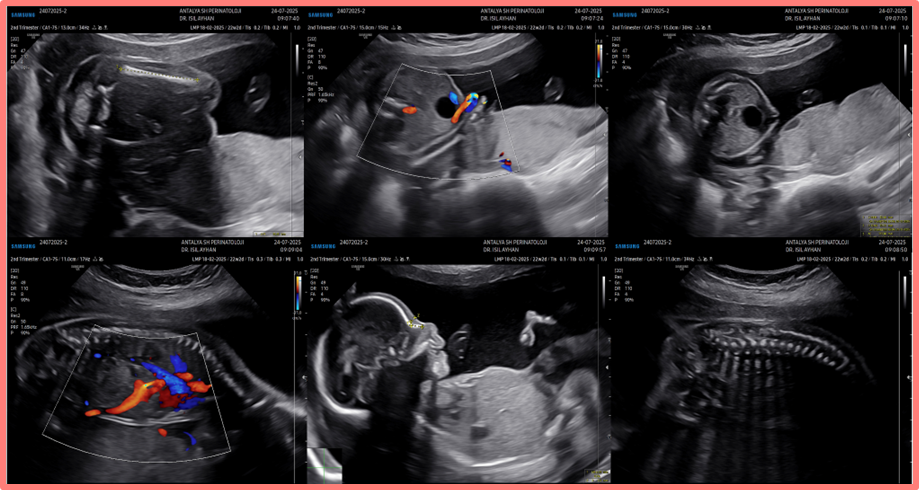

İkinci Trimester Anatomi Taraması Görüntüleri

Sakrokoksigeal teratomlar fetüste en sık görülen tümörlerdir, predominant şekilde kız fetüslerde daha çok görülür (Male to female oran 1:4). Sınıflamada Altman Sınıflaması kullanılır ve 4 tipe ayrılır. Tip 1 predominant olarak eksternalken, Tip 4 tamamen internaldir ve genellikle erken çocukluk dönemine kadar bulgu vermez. Histopatolojik olarak da matür, immatür ve malign olarak üçe ayrılırlar. Sıklıkla 2. trimesterde tanı alırlar, tamamen kistik, kistik/solid veya tamamen solid olabilirler. Tümörün davranışı öngörülemez olduğundan tanı anında predominant olarak kistik olan bir sakrokoksigeal teratom termde solid olabilir. Altman’ın orijinal çalışmasında tüm sakrokoksigeal teratomlar içinde %10 olarak raporlanan tip 4 sıklığı, daha güncel çalışmalarda %28 olarak verilmiştir—bu artış ultrason teknolojisi ve prenatal tanıdaki iyileşmelere bağlanabilir (1,2). Bu olguda, ikinci trimester anatomi taramasında özellik olmamasına rağmen 36. haftada intraabdominal büyük kistik kitle izlenmiş, kitlenin üreterlere bası etkisi nedeniyle görülen obstrüktif üropati/hidronefroz ve anhidramniyoz bulguları, kitlenin yeri ve kistik predominansı nedeniyle alt üriner sistem obstruksiyonu (LUTO) lehine yorumlanmıştır. Postnatal tanı sonrası ikinci trimester anatomi taraması görüntüleri tekrar incelenmiş ancak solid veya kistik bir intraabdominal kitle görülememiştir. Hastanın ikinci trimester ile 36 hafta arasında 4 kez daha gebe takip polikliniği prenatal viziti mevcut, ancak bu görüntülere ulaşılamamıştır. İkinci trimester ve sonraki takiplerde küçük olan bir teratom sonraki haftalarda aşırı büyümüş olabilir veya teratom natürü değişmiş olabilir. Her koşulda, bu olgu ISUOG’un da önerdiği 3. trimester anatomi taramasının önemini ve hastalara ikinci trimesterde verilen danışmanlıkta dikkatli olunması gerektiğini vurgulamaktadır (3).